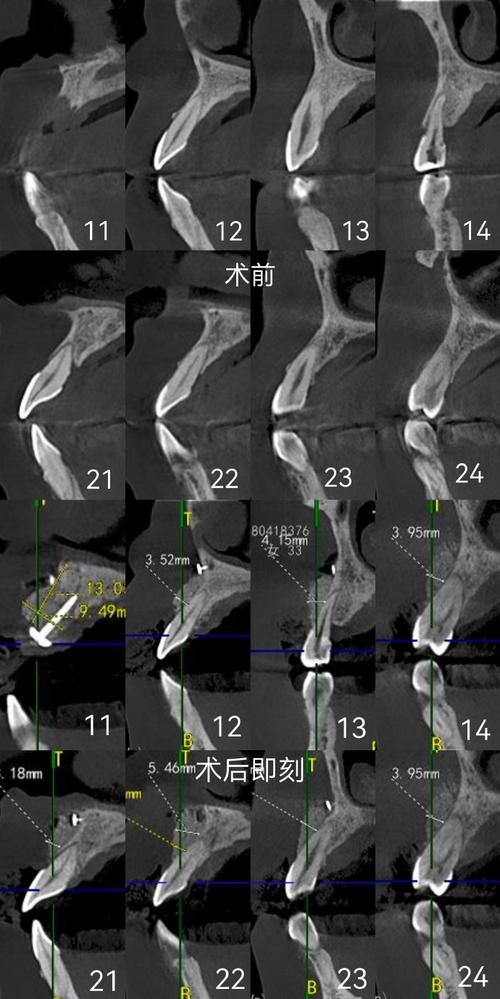

通常在PAOO手术前,正畸医生会进行短期的术前正畸,目的是排齐牙弓、建立初步的咬合关系,为手术创造更理想的条件,并确保术后牙齿能顺利移动到预定位置。